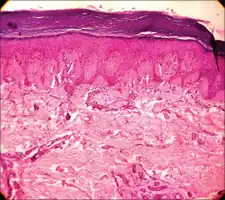

Laugier–Hunziker syndrome (/ˈloʊʒieɪ ˈhʊntsɪkər/) is a cutaneous condition characterized by hyperpigmentation of the oral mucosa,[1] longitudinal melanonychia,[1] and genital melanosis.[2]

The hyperpigmentation presented in Laugier-Hunziker syndrome is benign and should be differentiated from Peutz-Jeghers syndrome.